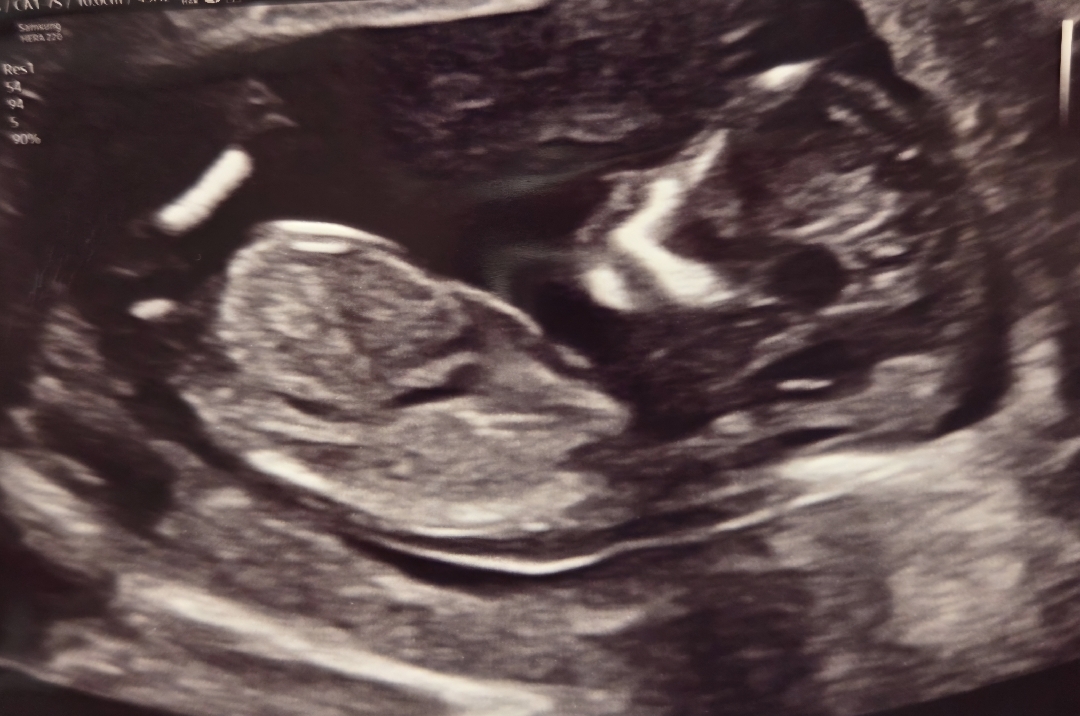

13주 4일차 각도법 문의드려요!

안녕하세요! 사진이 잘 보일지 모르겠지만.. 혹시 각도법 봐주실 수 있을까요??